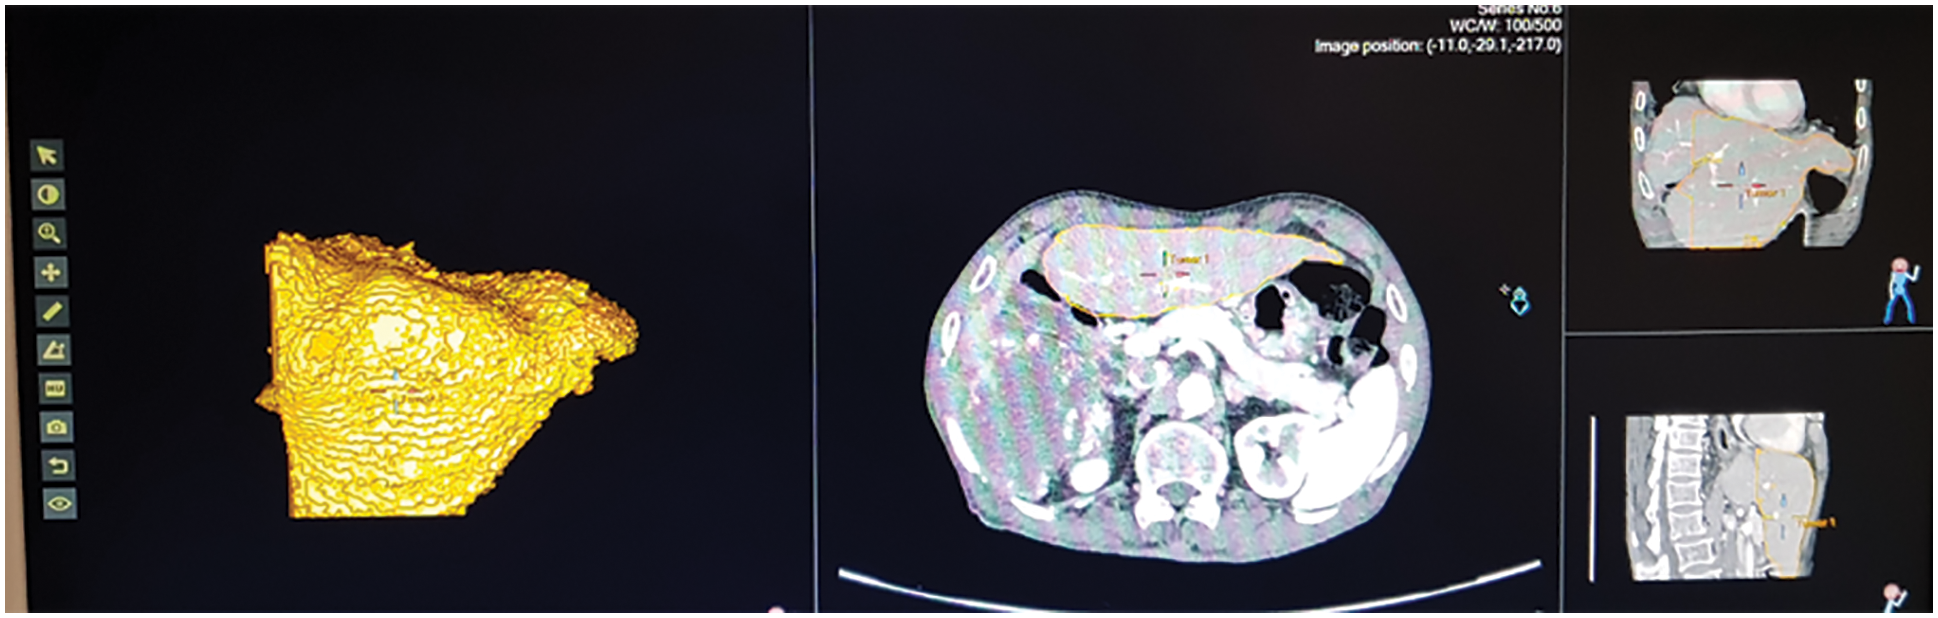

Fig. 13 shows the ultrasound value of medium fatty liver patient. The total liver volume is 1467 cc, right liver volume is 445.9 cc and left liver volume is 1021.88 cc. The medium fatty liver signal obtained from male patient age 70. Fig. 14 shows the ultrasound of mild fatty liver patient. The total liver volume is 961.86 cc, right liver volume is 365.93 cc and left liver volume is 595.33 cc. The mild fatty liver male patient at age 70. The signals from fatty liver are obtained from fatty liver sensor for sever mild and moderate fatty liver patients. The statistical parameters of the fatty liver signal from TQWT and the ultrasound lab values are correlated using gaussian regression modelling.

Figure 14: Ultrasound of mild fatty liver patient